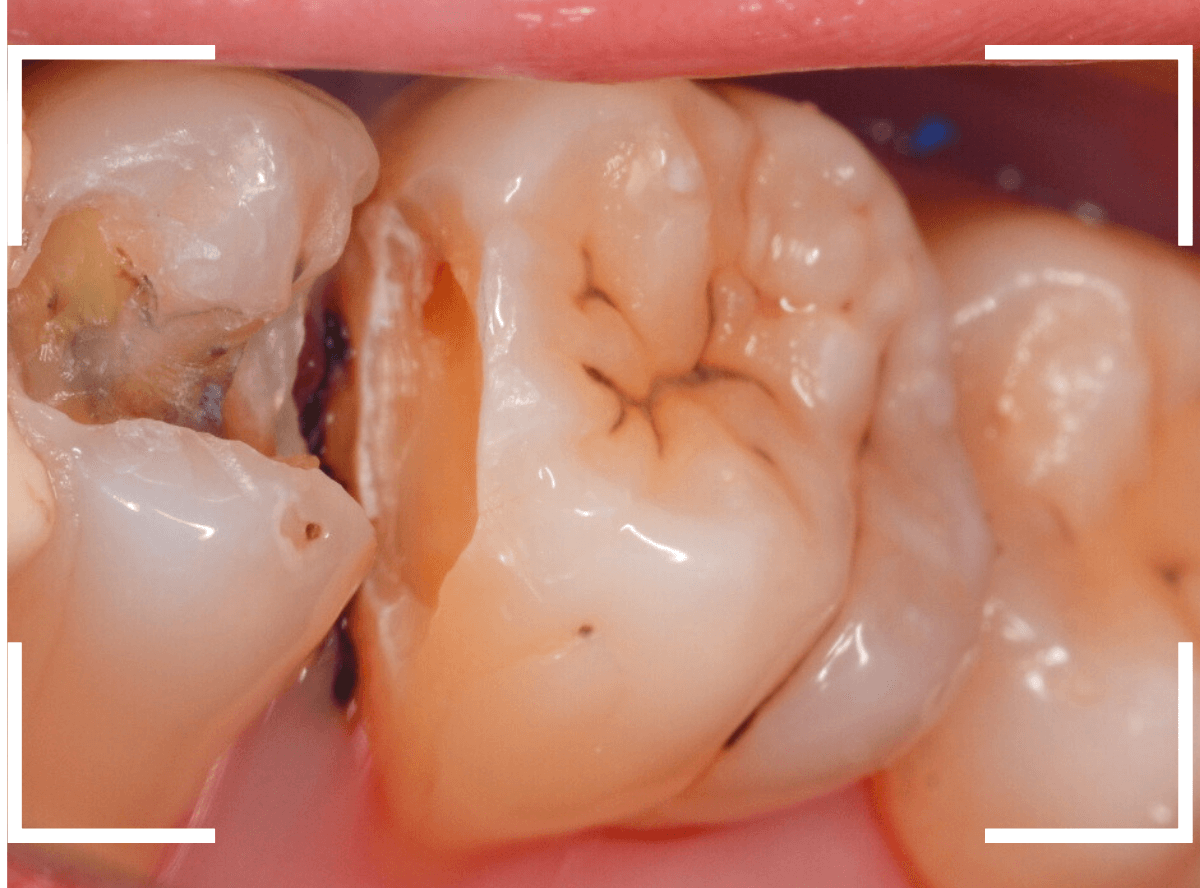

Case.23 歯のすきまから両側が大きな虫歯

「下の奥歯が痛む」という訴えで来院された患者さんのケースです。

目視でも、手前の奥歯がかけていて、中で虫歯が広がってるであろうことは予想できます。

ピンセットで歯を叩いてみても、手前の奥歯が痛むようです。

レントゲン写真で確認します。

青い線が神経、赤い線が虫歯の範囲です。

奥歯の方がより深い虫歯に見えますが、再度打診で確認したところ、やはり手前の奥歯が痛むそうです。

状況から、まず手前の奥歯から治療となりました。